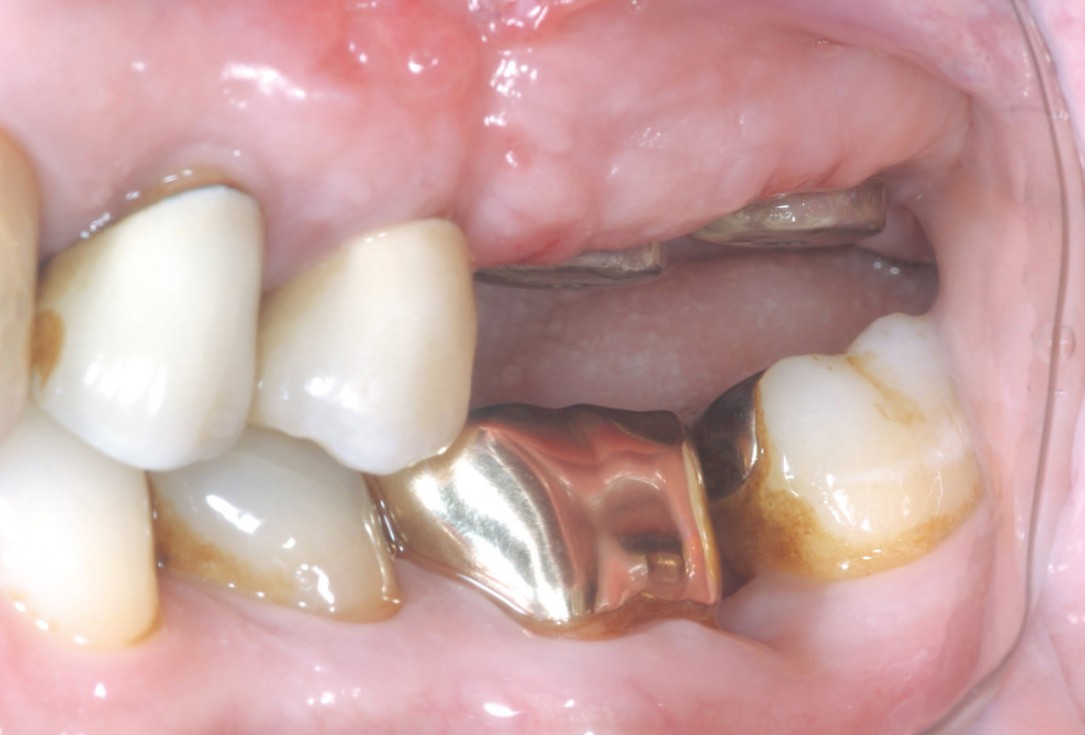

14/15 - Final prosthetic restoration- proper implant-crown ratio compared to the neighboring teethTreatment of a combined horizontal and vertical bone defect in the maxilla with maxgraft® cortico in the allogenic shell technique - Dr. R. Würdinger